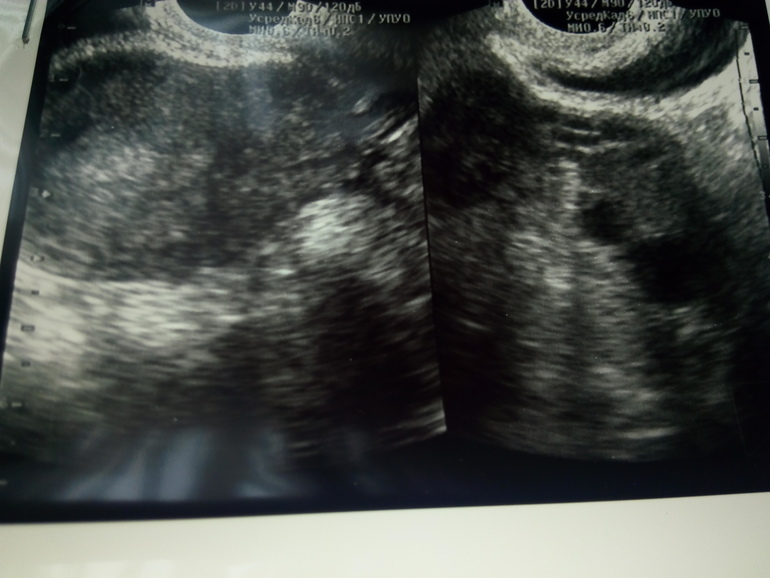

Полип эндометрия

Процедуры и лечениеСходила на узи Г поставила диагноз полип эндометрия. Сказала что с месячными может выйти. Есть такие у кого он вышел с М или все же без операции ни как?